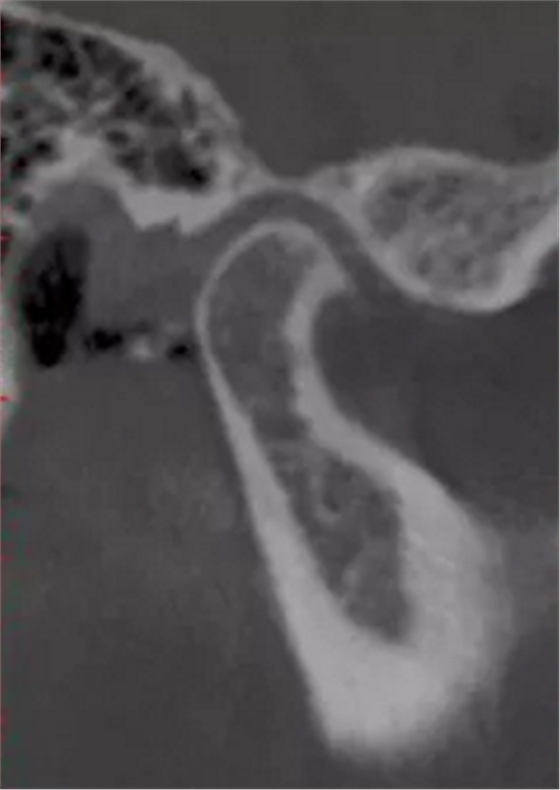

更嚴重的是會影響下頜關(guān)節(jié)的健康,正常下頜運動三模式開口運動,側(cè)方咬合,前伸下頜,閉鎖合時只留開口運動模式了,其他二種只有先開口后才能發(fā)生。這樣由于上前牙內(nèi)傾,強迫下頜后退,使下頜關(guān)節(jié)位置異常,關(guān)節(jié)頭越磨越平。這類人群往往有關(guān)節(jié)區(qū)疼痛、張閉口彈響,張不開口等,嚴重的會影響日常生活和情緒。

關(guān)節(jié)頭損傷